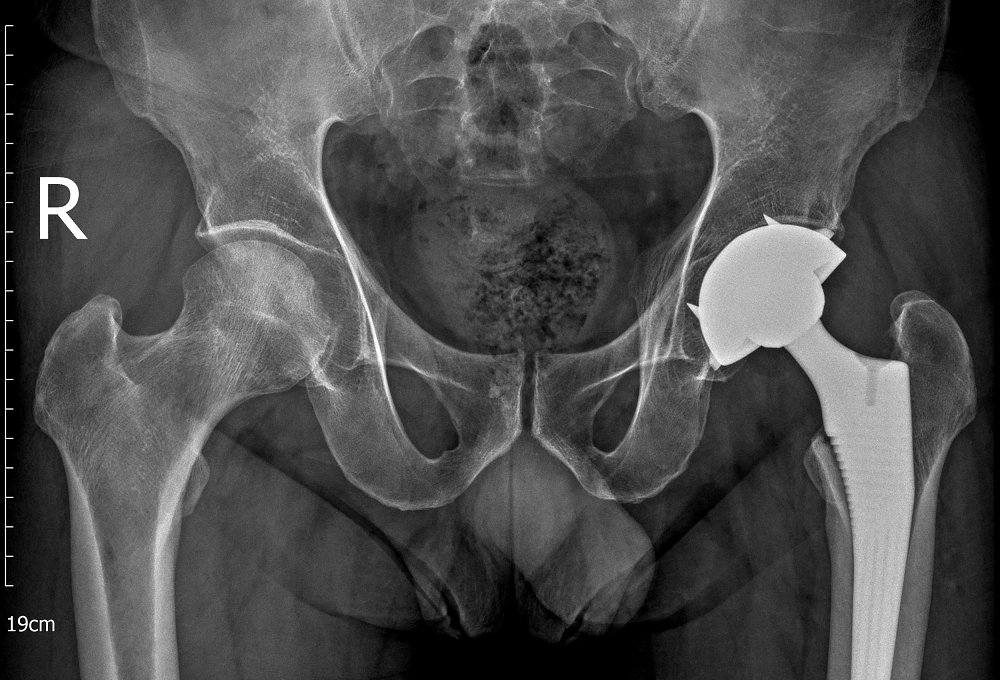

Qua thăm khám lâm sàng kết hợp chẩn đoán hình ảnh như X-quang và MRI, các bác sĩ xác định người bệnh bị hoại tử chỏm xương đùi hai bên, trong đó khớp háng bên trái đã tổn thương nặng hơn. Kết quả chẩn đoán của bác sĩ khiến người bệnh bàng hoàng.

Bệnh nhân được bác sĩ thực hiện thành công cuộc phẫu thuật thay khớp háng toàn phần bên trái

Với trường hợp này, khớp háng trái đã tiến triển đến giai đoạn nặng, không còn khả năng bảo tồn, các bác sĩ buộc phải chỉ định thay khớp háng toàn phần nhằm giảm đau, phục hồi chức năng vận động và tránh nguy cơ tàn phế cho người bệnh. Trong khi đó, khớp háng bên phải vẫn còn khả năng bảo tồn nên các bác sĩ lựa chọn phương pháp phẫu thuật giảm áp cổ xương đùi để cải thiện tuần hoàn, làm chậm quá trình hư khớp.

Ca phẫu thuật thay khớp háng bên trái được thực hiện thành công. Chỉ sau một ngày, người bệnh đã có thể ngồi dậy, co duỗi háng và tập phục hồi chức năng. Sau 48 giờ, ông P. đi lại được mà không cần trợ giúp, mức độ đau giảm rõ rệt. Ba tuần sau, khi khớp háng bên trái đã ổn định, người bệnh tiếp tục được phẫu thuật giảm áp cổ xương đùi bên phải. Nhờ can thiệp đúng thời điểm, khớp háng còn lại được bảo tồn giúp ông P. đi lại bình thường, không còn tình trạng dáng đi khập khiễng.